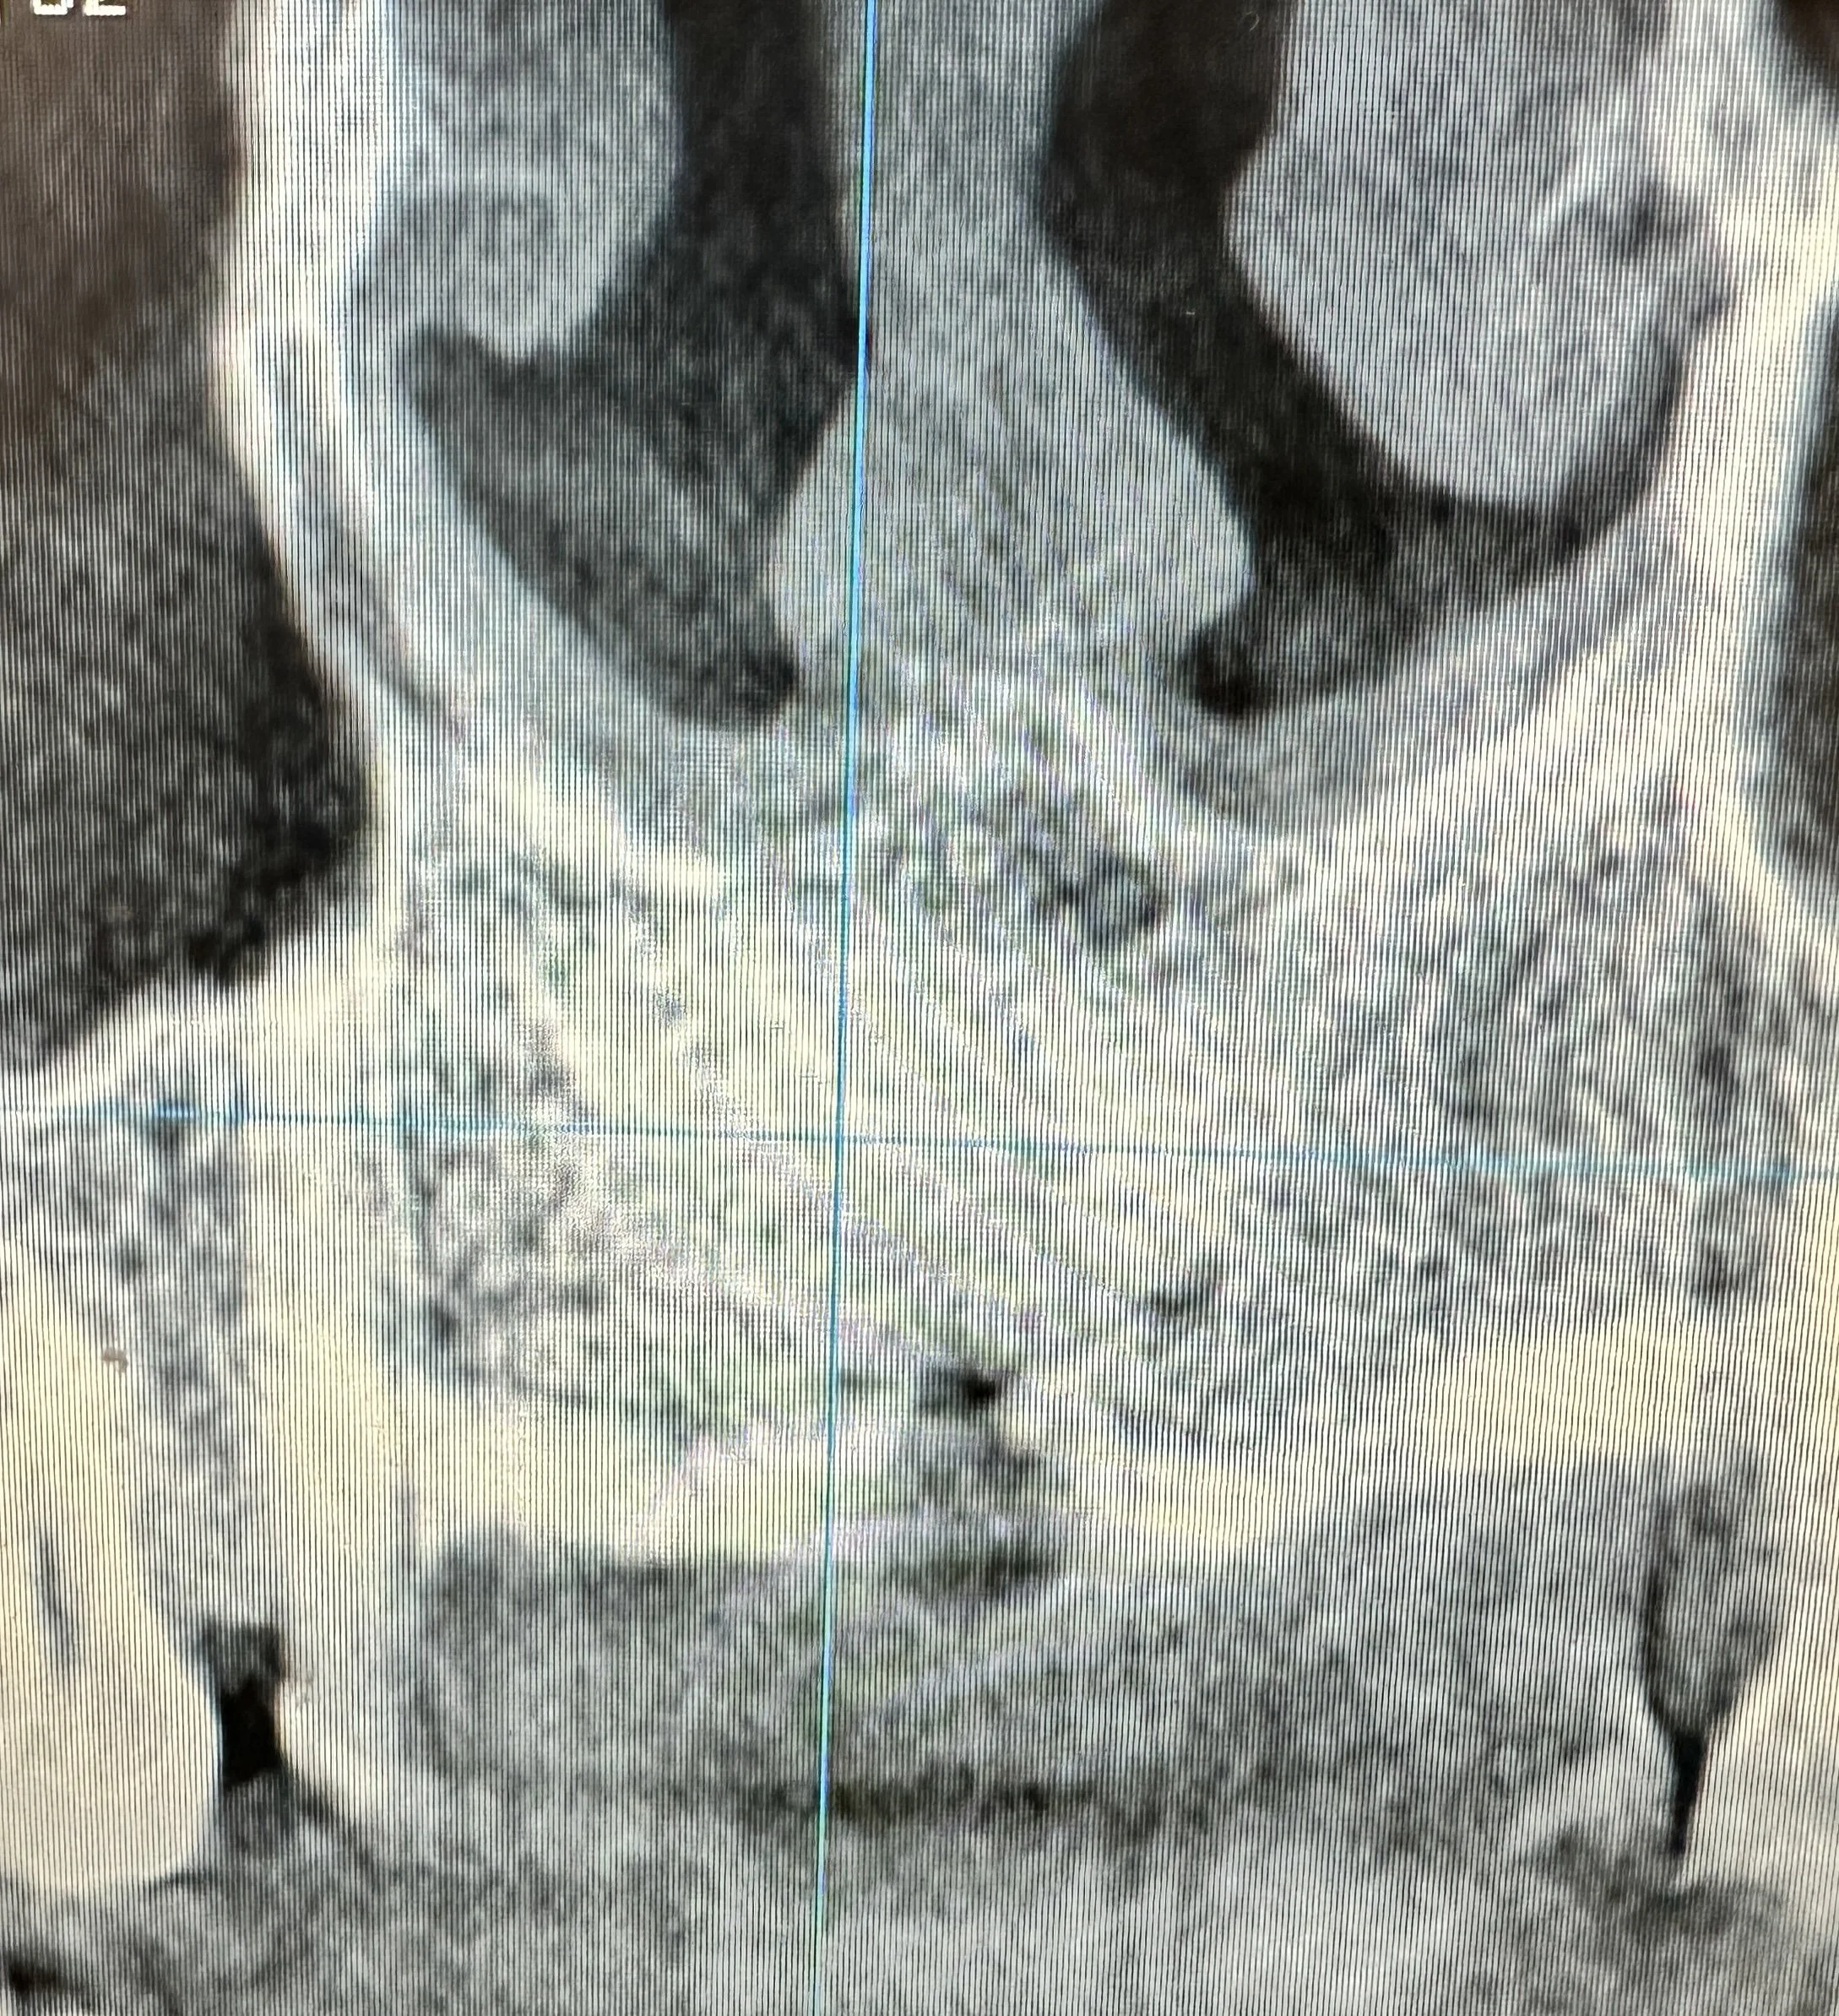

A patient presented with a large cystic lesion associated with tooth #8, resulting in significant bone loss extending from the apical third of the root to the nasal sinus floor. Advanced imaging also revealed mesial root resorption of tooth #8.

Tooth #8 was extracted, and the cyst was carefully enucleated. The extent of bone loss included destruction of the buccal bony wall and involvement of the palatal wall. To reconstruct the site and preserve the ridge architecture, a resorbable collagen membrane was first placed along the palatal wall. A mineralized cortico-cancellous particulate bone graft was then gently packed into the area of bone destruction to restore volume and support future regeneration.

Post-operative CT imaging confirmed successful placement of the graft material in the previous area of bone destruction. The resorbable membrane served to prevent soft-tissue ingrowth and maintain graft stability during the healing phase, allowing bone turnover to occur gradually as the graft resorbed and new bone formed.